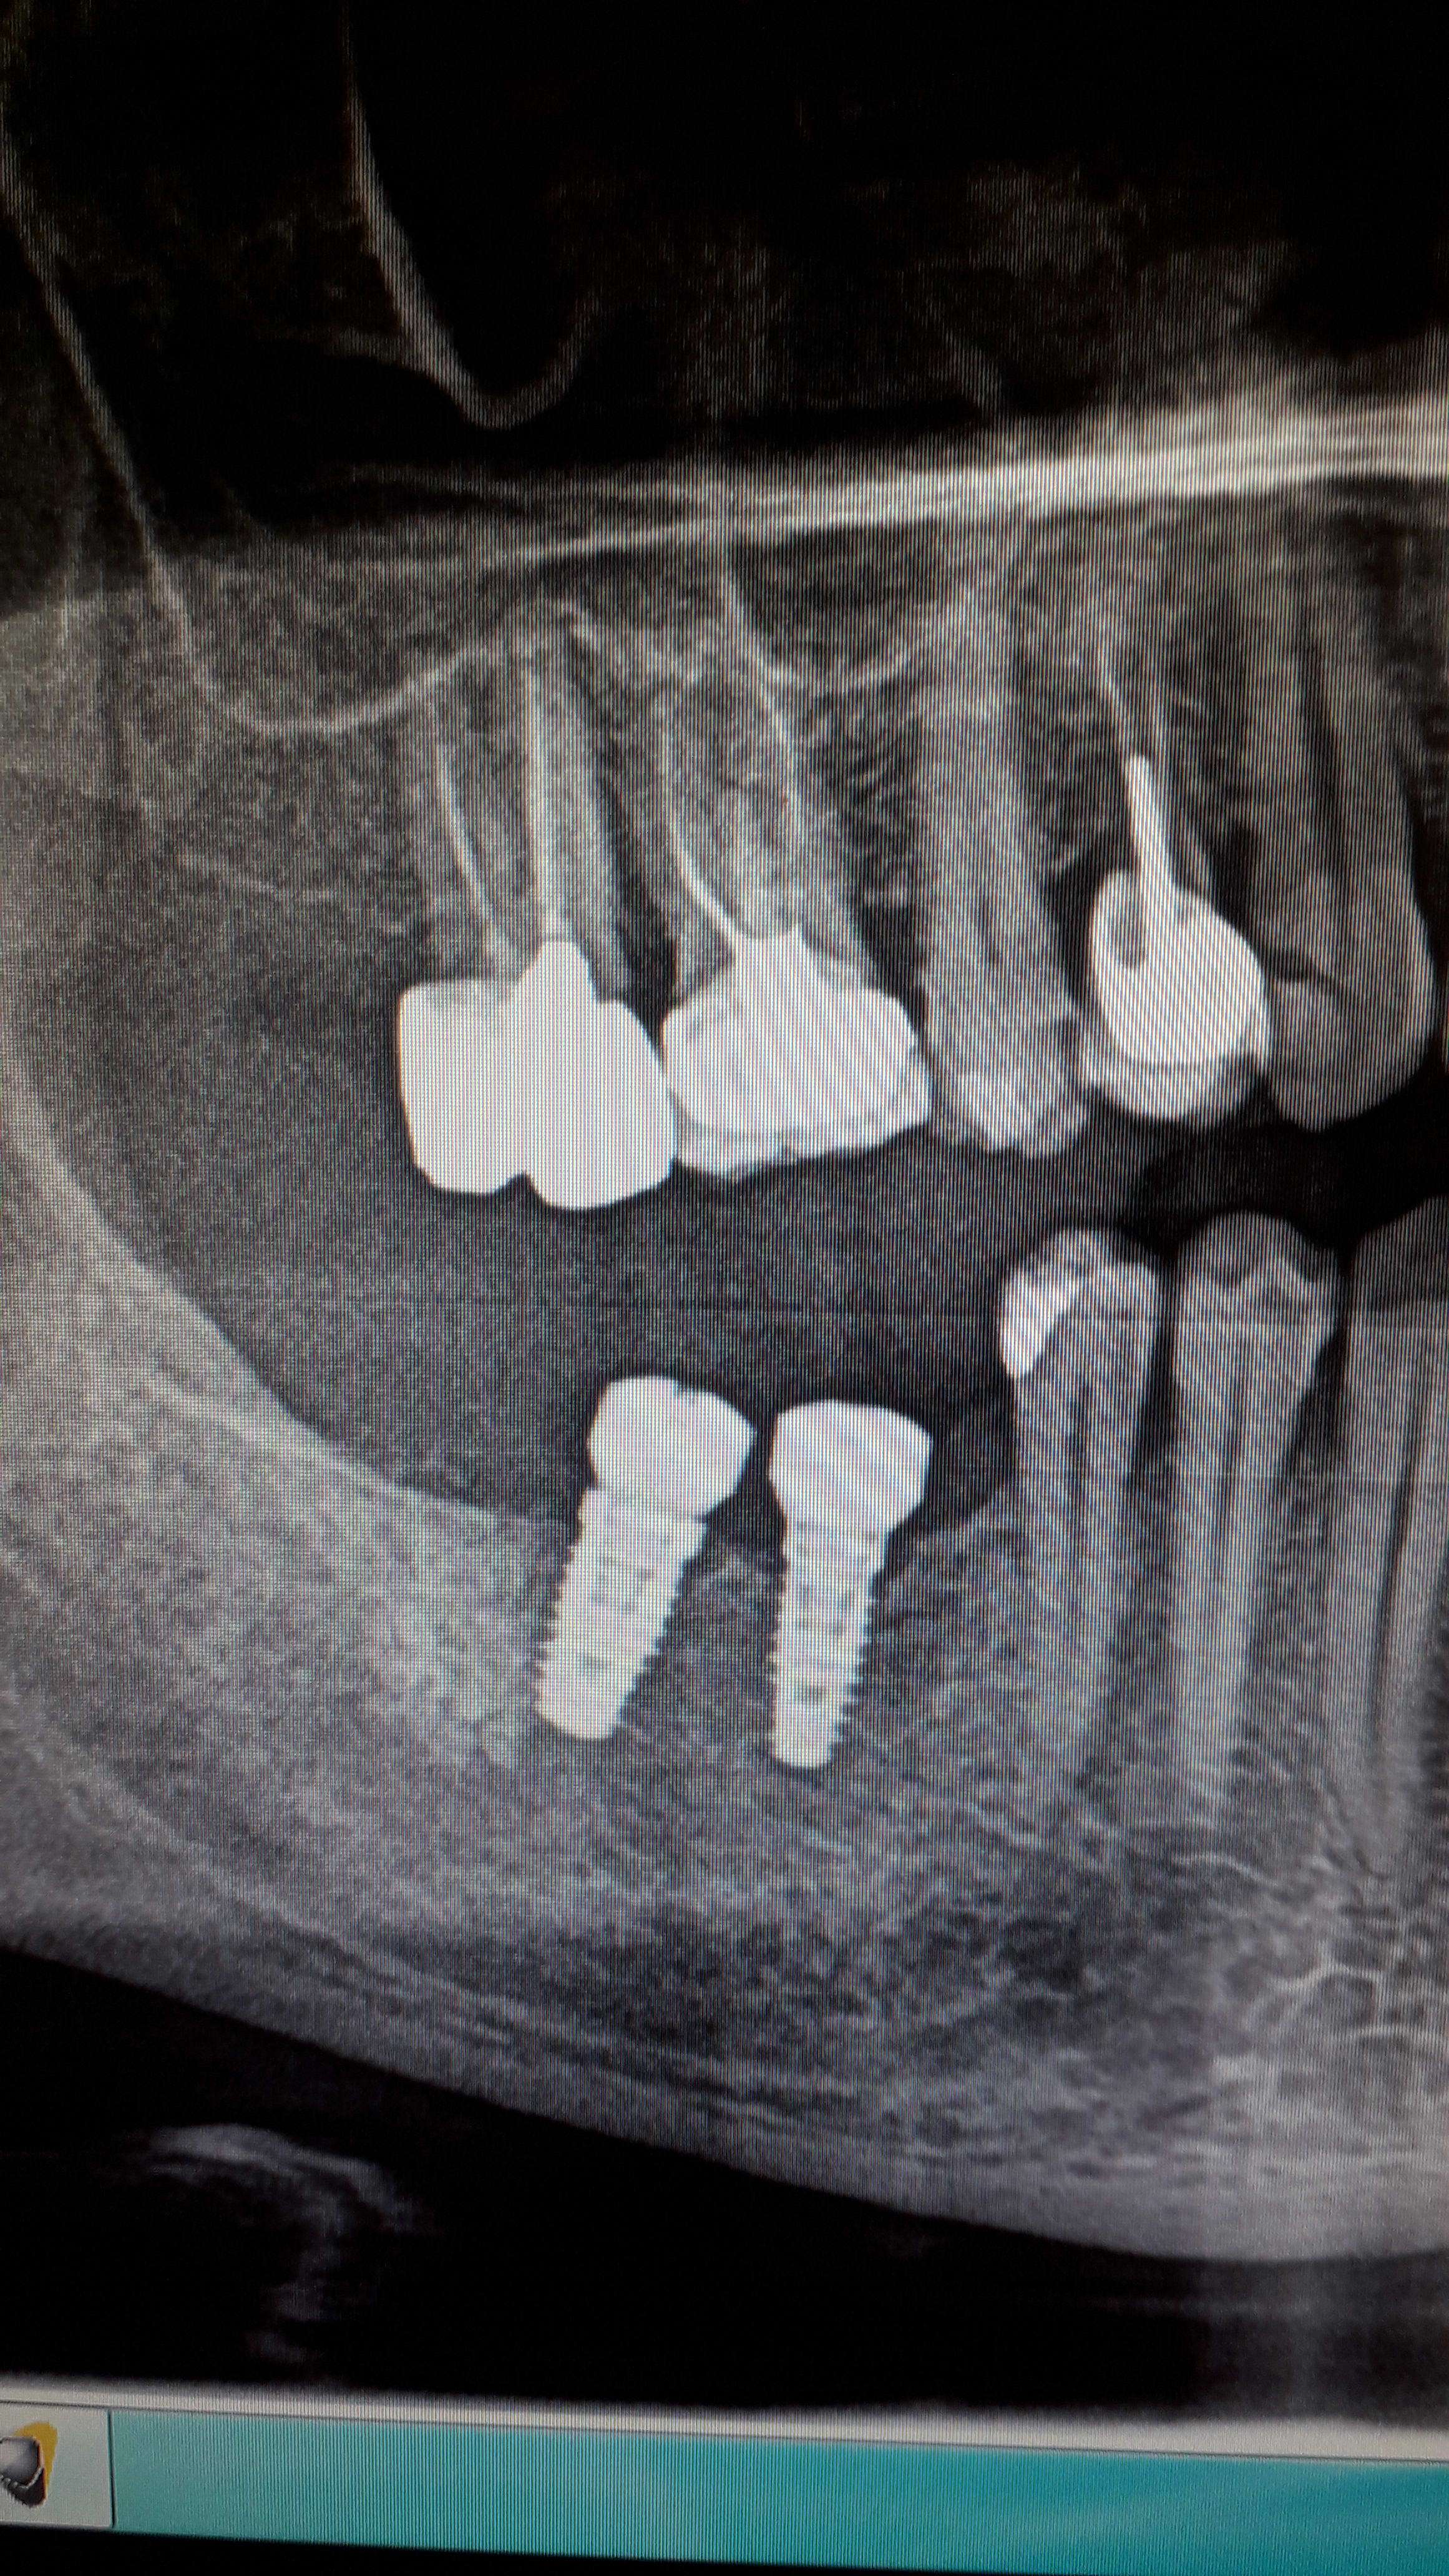

Un nouveau patient est venu au cabinet afin que je fasse les coiffes sur ses implants posés il y a 2 ou 3 ans mais il n a pas de fiche de traçabilité et ne se rappelle plus de qui les lui a posé.

J ai fait des photos... si jamais quelqu' un reconnaît la marque... Ce serait génial.!

Biomet 3i osseotite

Et on remarquera cette petite lyse osseuse autour des cols des biomet ... très souvent on a ce genre de radios avec perte osseuse juste sous le col .

Effectivement j ai parlé de la lyse osseuse ...